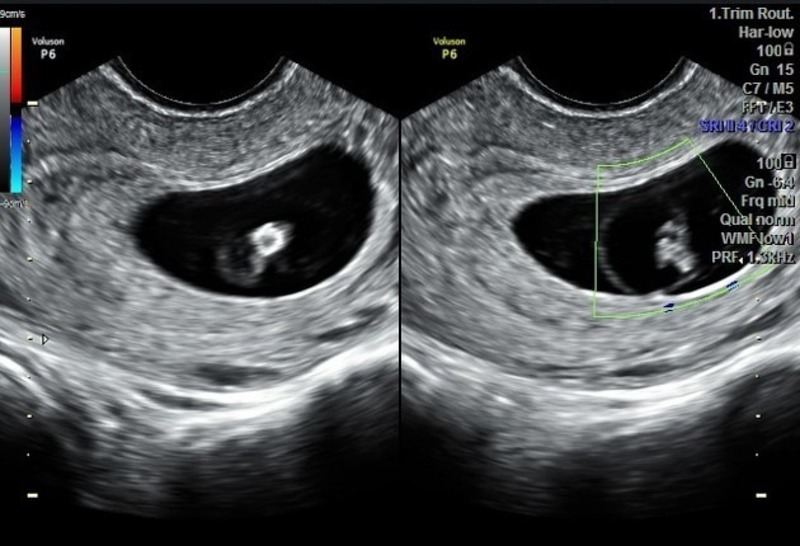

Hiện tượng xuất hiện yolksac trong siêu âm thai là dấu hiệu sớm cho thấy phôi thai đang phát triển bình thường trong tử cung. Yolksac thường được nhìn thấy ở tuần thai thứ 5 – 6 thông qua siêu âm đầu dò, xuất hiện dưới dạng một vòng tròn nhỏ, sáng bên trong túi thai. Sự có mặt của yolksac chứng tỏ quá trình thụ tinh và làm tổ đã thành công, là bước quan trọng trước khi quan sát thấy tim thai. Nếu sau tuần thứ 6 túi thai không xuất hiện yolksac, bác sĩ có thể nghi ngờ thai ngoài tử cung hoặc thai lưu.

Yolksac trong siêu âm thai hoàn toàn không nguy hiểm mà ngược lại còn là dấu hiệu tích cực cho thấy thai đang phát triển bình thường. Đây là cấu trúc tự nhiên và cần thiết trong giai đoạn đầu của thai kỳ, giúp nuôi dưỡng phôi khi nhau thai chưa hoàn thiện. Tuy nhiên, nếu yolksac có hình dạng méo mó, quá to hoặc quá nhỏ (thường >6 mm hoặc <2 mm) có thể là dấu hiệu cảnh báo bất thường trong quá trình phát triển của thai nhi. Khi bác sĩ phát hiện yolksac bất thường, thường sẽ chỉ định theo dõi sát và kiểm tra lại bằng siêu âm ở các tuần tiếp theo.